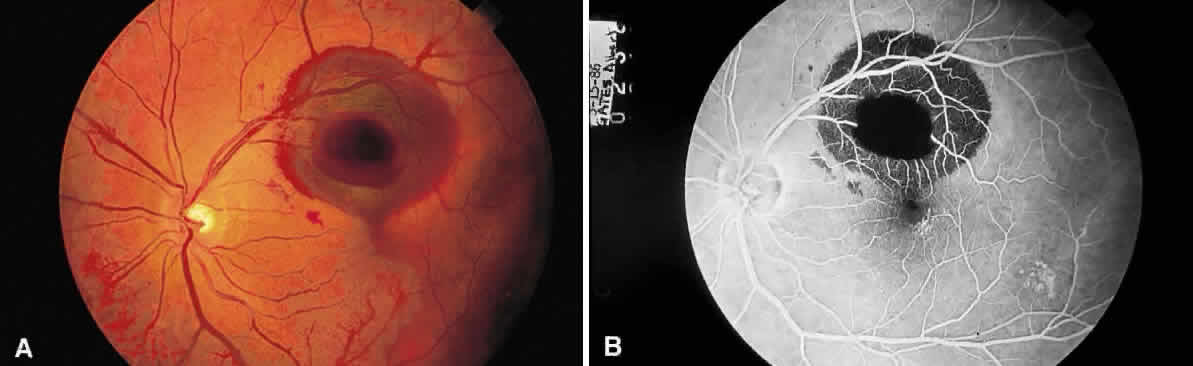

A hemorrhage in the nerve fiber layer (Fig. 11A) dissects along the plane of the layer parallel to the orientation of the internal limiting membrane (see Fig. 11B). A hemorrhage located between the retinal pigment epithelium and Bruch's membrane also spreads in a plane parallel to the orientation of the membrane (Fig. 12). However, its extent is limited by the adhesion of the pigment epithelium to Bruch's membrane, in contrast to a nerve fiber layer hemorrhage, where no such delineating structure is present. Therefore, a fresh nerve fiber layer hemorrhage appears bright red and has feathery borders, whereas a subpigment epithelial hemorrhage appears brown-black and has sharp borders (Fig. 13).

Fig. 11. A. Section of retina with hemorrhage in the nerve fiber layer (between the two large arrows). Notice that the limits of the hemorrhage are not clearly defined, since scattered red blood cells can be seen to the right of the right-hand large arrow. This histologic picture corresponds to a clinically observed fame-shaped hemorrhage with an indistinct border. The detached posterior hyaloid is marked by four small arrows. B. Fundus photograph of nerve fiber layer hemorrhage. They are oriented parallel to the plane of the internal limiting membrane. Because of their dispersal within the ganglion cell layer, the borders are “feathery” (flame shaped).

Fig. 12. Section of the eye showing subretinal hemorrhage. (Courtesy of Ralph C. Eagle Jr, MD, Philadelphia, PA)

Fig. 13. A. Fundus photograph of a subpigment epithelium hemorrhage superotemporal to the disc secondary to a macroaneurysm. Notice its dark color and sharp border. The central portion of the hemorrhage has extended through the sensory retinal to the subinternal limiting membrane area. B. Fluorescein angiography showing the retinal vessels overlying the deep hemorrhage but obscured by the central extension anteriorly. (B, courtesy of William Tasman, MD, Philadelphia, PA)